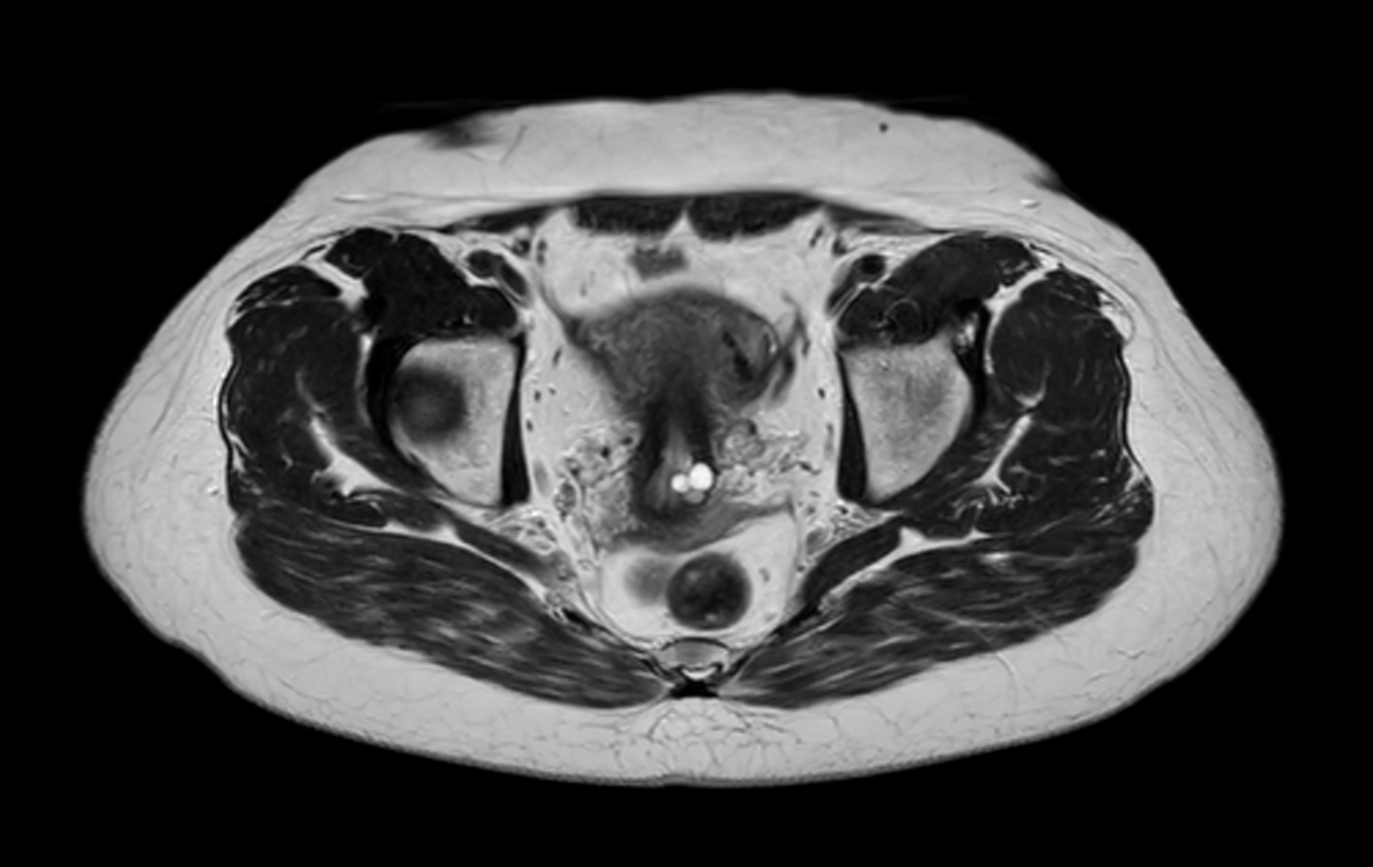

Axial T2w TSE